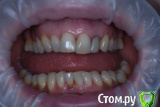

VVQW Опубликовано 25 октября, 2016 Поделиться Опубликовано 25 октября, 2016 (изменено) добрый день. Сложная ситуация. Более 10 лет назад ставили брекеты без анализов, диагностик, снимков и пр. Сейчас, что имееем, то и имеем. Большую проблему. Прикуса нет. Клиновидки из-за перегруза. Что можно сделать прошу совета и помощи. Обращалась за консультацией ко многим специалистам, мнения разнятся от слегка положительного, до просто критической ситуации. Последний профессор ортодонт вообще сказал - все вырвать и поставить протезы. УЖАС..... Может кто-нибудь из врачей даст совет... очень на Вас надеюсь. С уважением. Изменено 25 октября, 2016 пользователем VVQW Ссылка на комментарий

VVQW Опубликовано 6 декабря, 2016 Автор Поделиться Опубликовано 6 декабря, 2016 (изменено) Лечение скорее всего будет неким компромисом. Я правильно понимаю, 10 лет назад сняли брекеты?Брекеты были сняты более 10 лет назад. Ретейнеры не ставились. Верхние 6-ки по решению врача были убраны для задвигания зубов к заду, верхние 8-ки - не выросли. Нижние 6-ки - удалены в подростковом возрасте, до 14 лет. http://s019.radikal.ru/i641/1612/eb/3498e6cec3f8.jpg http://s018.radikal.ru/i518/1612/73/739600b6d2d1.jpg http://s011.radikal.ru/i318/1612/73/443e1513aaf8.jpg http://s017.radikal.ru/i403/1612/86/73e0dfe4ca62.jpg http://s018.radikal.ru/i518/1612/a2/bd7078537d9e.jpg http://s017.radikal.ru/i417/1612/9d/41b6d1c98666.jpg http://s019.radikal.ru/i642/1612/fe/3222fa19d517.jpg Гипсовых моделей нет, зубы неподвижны. http://s019.radikal.ru/i639/1612/56/1345f17db908.jpg http://s019.radikal.ru/i630/1612/55/145ef7c813b2.jpg http://s017.radikal.ru/i440/1612/c2/74bd4da2643e.jpg http://s008.radikal.ru/i303/1612/b4/e80683ed7d2b.jpg http://s010.radikal.ru/i314/1612/74/6d2f9671b0d5.jpg http://s018.radikal.ru/i502/1612/97/9a15fcf4ddd3.jpg http://s020.radikal.ru/i715/1612/59/9bb4a006621f.jpg Изменено 6 декабря, 2016 пользователем VVQW Ссылка на комментарий

VVQW Опубликовано 6 декабря, 2016 Автор Поделиться Опубликовано 6 декабря, 2016 Брекеты были сняты более 10 лет назад. Ретейнеры не ставились. Верхние 6-ки по решению врача были убраны для задвигания зубов к заду, верхние 8-ки - не выросли. Нижние 6-ки - удалены в подростковом возрасте, до 14 лет.зубы неподвижны. Ссылка на комментарий